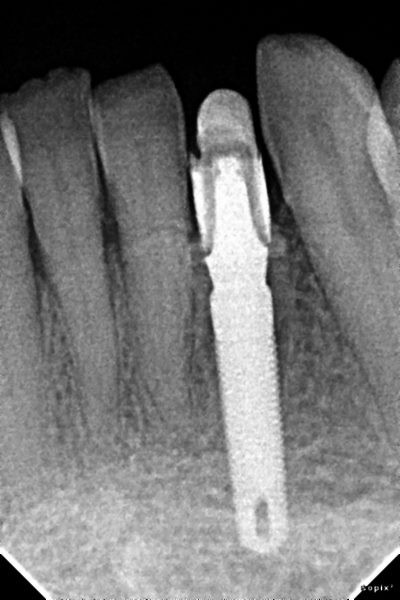

Colocación de implante y carillas libres de metal

Envíado por Grupo Dental de El Salvador